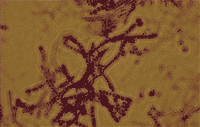

| Rys. 8 Termofilne promieniowce (Saccharopolyspora rectivirgula) (synonimy: Micropolyspora faeni, Faenia rectivirgula) Zdjęcie w mikroskopie świetlnym, x 1000 |

Szczególne znaczenie jako przyczyna zawodowych chorób alergicznych mają termofilne promieniowce (Rys. 8), nitkowate bakterie uznawane za główną przyczynę najbardziej znanej formy (podjednostki) AZPP określanej jako „płuco rolnika”, lub „płuco farmera”.

Głównym źródłem chorobotwórczego alergenu są gatunki: Saccharopolyspora rectivirgula (synonimy: Micropolyspora faeni, Faenia rectivirgula), Thermoactinomyces vulgaris, Thermoactinomyces thalpophilus i Saccharomonospora viridis. Są to nitkowate bakterie, rozwijające się w przemokniętych paszach (głównie sianie) o dużej zawartości wody (30÷46 %), w których następuje proces samozagrzewania do temperatury 55÷70 oC. Do uczulenia dochodzi w trakcie pracy z przegrzaną paszą, w wyniku wdychania pyłu zanieczyszczonego drobnymi (ok. 1 µm średnicy) zarodnikami promieniowców [20].